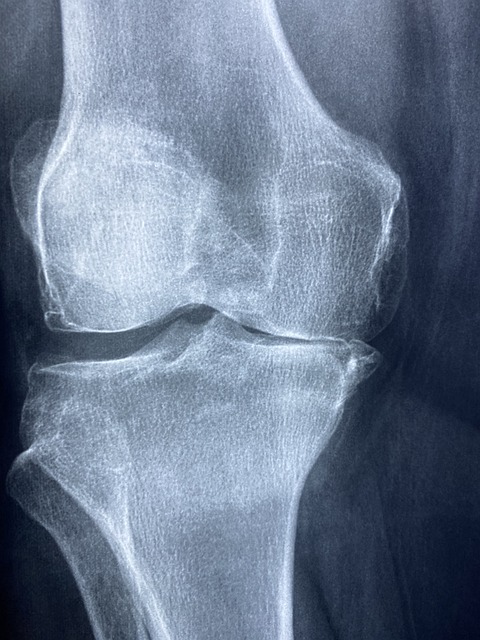

- 골다공증 예방: 연구에 따르면, 우슬은 뼈의 밀도를 증가시키고 골 손실을 방지하는 데 도움을 줄 수 있습니다. 이는 골다공증이나 다른 뼈 관련 질환을 예방하거나 관리하는 데 유익할 수 있습니다.